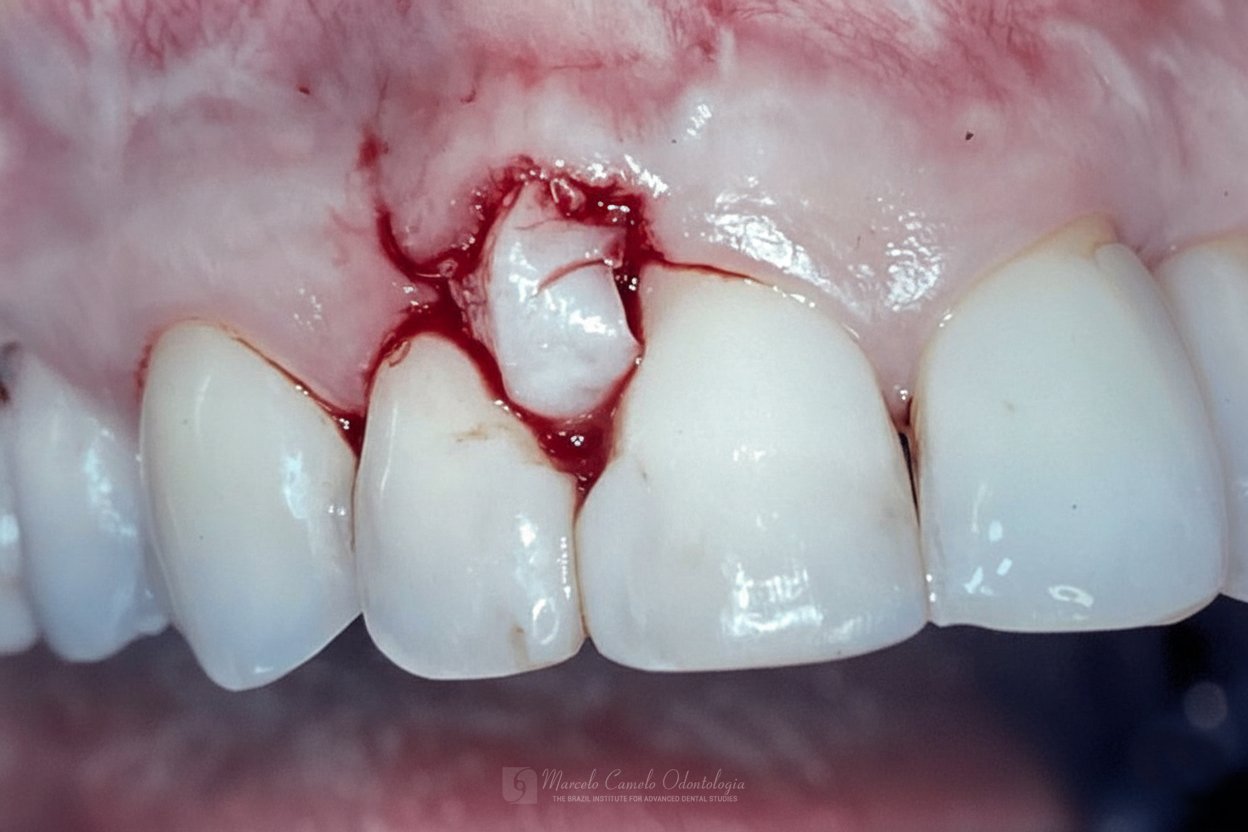

Para casos com boa qualidade de mucosa queratinizada, um envelope vestibular recebe a porção desepitelizada do enxerto pediculado.